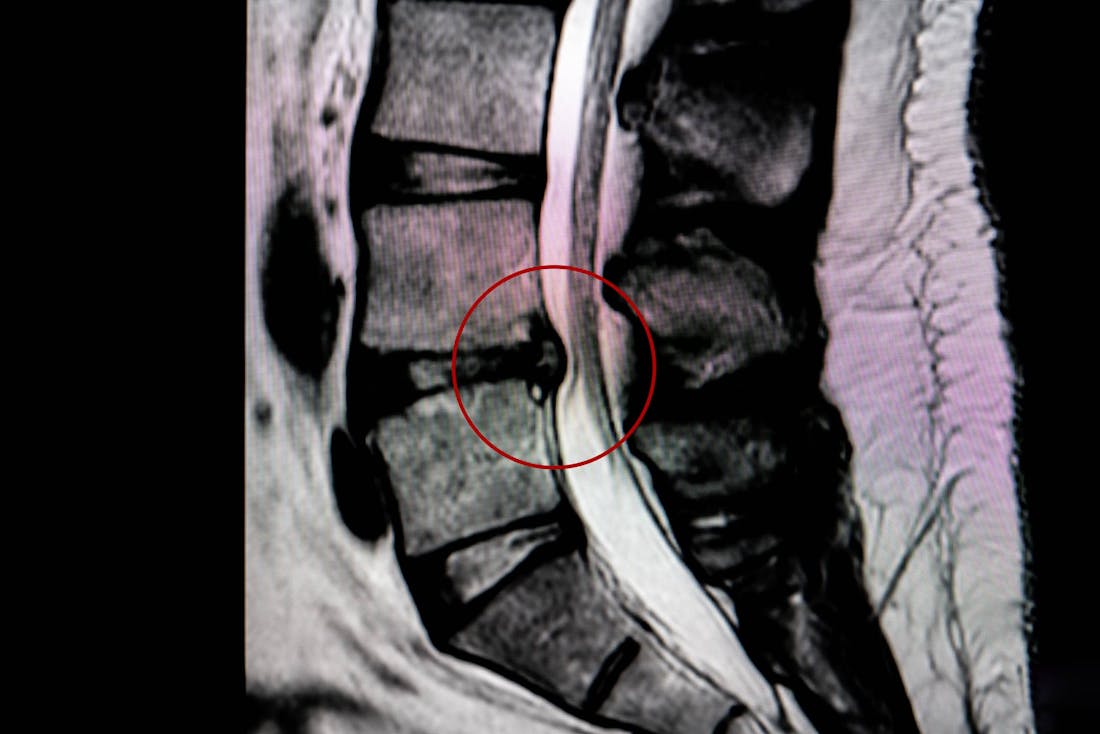

Herniated Disc

Suffering from a herniated disc can result in shooting pain, tingling, or weakness in the affected area. The Center for the Functional Restoration of the Spine employs a multidisciplinary approach, combining physical therapy, pain management, and minimally invasive procedures to alleviate symptoms and restore spinal function.